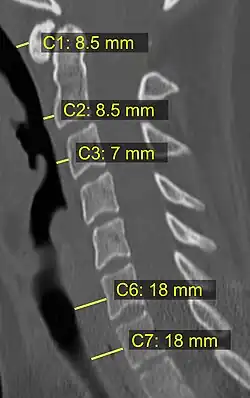

CT scan or X-ray images are evaluated for the presence or absence of directly visible fractures. In addition, indirect signs of injury by the vertebral column are incongruities of the vertebral lines,[11] and/or increased thickness of the prevertebral space:[12]

![CT scan with upper limits of the thickness of the prevertebral space at different levels.[12]](./CT_of_prevertebral_space.jpg)